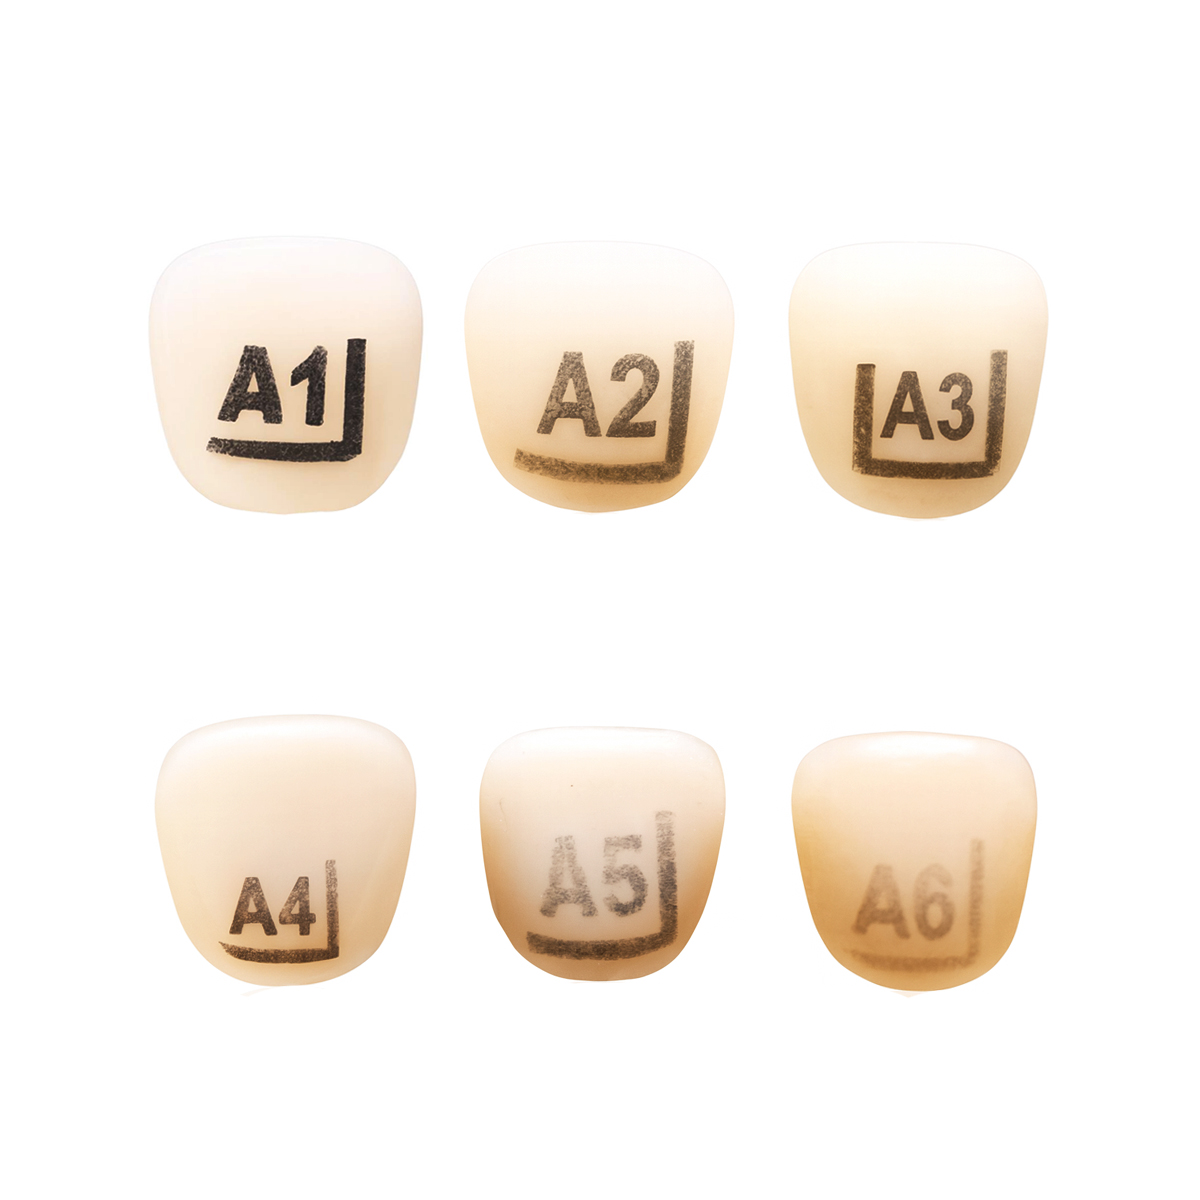

A: A pediatric dental crown, also known as a pedo crown, is a specialized dental restoration designed for children with primary (baby) or permanent molars that have suffered decay, damage, or fractures. These crowns are custom-fitted caps that cover the entire tooth, restoring its shape, strength, and function. Pediatric dental crowns are crucial in preserving the integrity of primary teeth, ensuring proper dental development, and preventing premature tooth loss in young patients. They are available in various materials, such as stainless steel, polycarbonate, and transparent strip, to suit different clinical needs and preferences.

A: On primary teeth, stainless steel crowns (SSCs) are commonly used. Stainless steel crowns are pre-fabricated crowns made of stainless steel material. They are durable, cost-effective, and can be easily adapted to fit the primary tooth's shape and size. These crowns are often used for molars and sometimes for anterior teeth when extensive restoration is needed.

A: Dentalkart offers a wide range of pediatric crowns, including stainless steel primary crowns, stainless steel primary molars, stainless steel permanent molars, polycarbonate crowns, and transparent strip crowns.

A: The choice of pediatric crown depends on various factors such as the tooth's position, size, and condition. Stainless steel crowns are ideal for posterior teeth, while polycarbonate crowns are suitable for anterior teeth. Transparent strip crowns are useful for esthetic concerns.